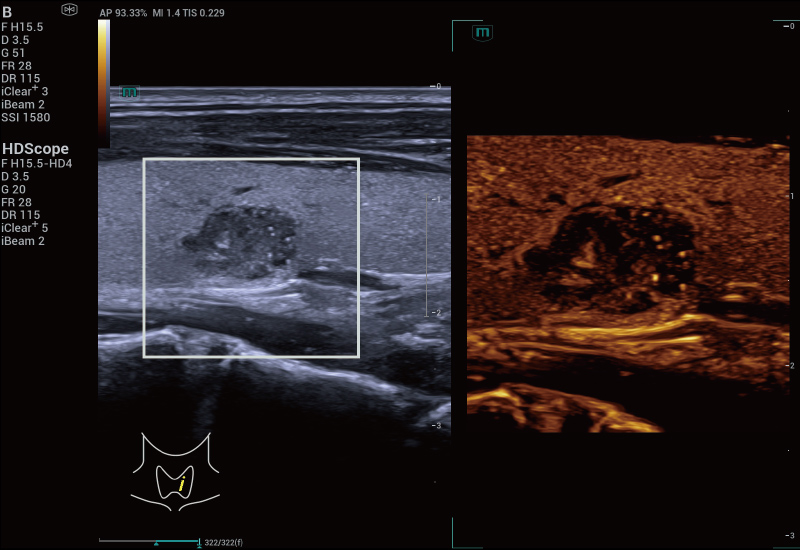

Grazie alla piattaforma AIT, Resona A20 offre una soluzione integrata completa per l'imaging a super-risoluzione, una capacit├Ā finora difficile da raggiungere. La SR CEUS rivela i dettagli intricati del microcircolo delle lesioni a livello di micron, favorendo gli studi di perfusione microcircolatoria in oncologia.

Risoluzione a livello di micron

Capacit├Ā di rilevamento microvascolare

Strumenti di quantificazione

Iperplasia nodulare focale | Mappa densit├Ā

Iperplasia nodulare focale | Mappa direzione

Iperplasia nodulare focale | Mappa velocit├Ā